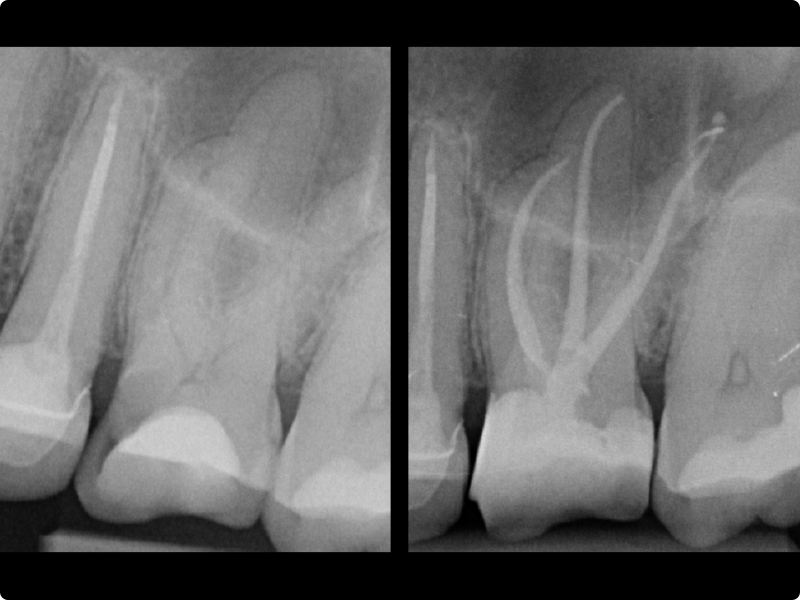

Three days of practical sessions with microscopes, exploring rotary and reciprocating systems, bioceramic sealers, and retreatment protocols for predictable, high-quality results.

• Canal shaping: general principles.

• Scouting, glide path, preflare.

• Continuous rotation and reciprocation.

• Management of calcified canals.

• Mechanical shaping of the canal body in continuous rotation and reciprocation on extracted teeth with access cavities previously prepared by the participant on anterior and posterior teeth.

• Manual scouting and achievement of the correct working length.

• Mechanical glide path and preflare.

• Shaping using rotary and reciprocating systems.